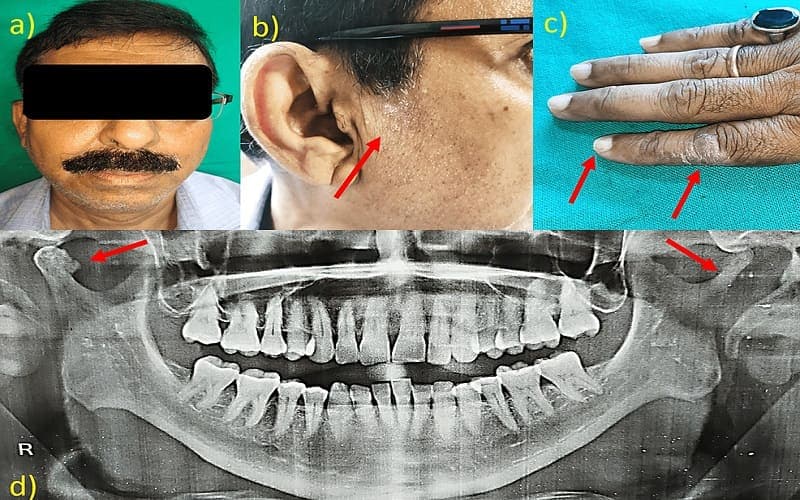

Để trả lời câu hỏi viêm khớp thái dương hàm có gây lệch mặt không, trước hết cần hiểu rằng khớp thái dương hàm là khớp giúp điều khiển vị trí hàm dưới và hoạt động của cơ nhai. Khi khớp này bị viêm hoặc rối loạn, có thể góp phần gây ra sự bất đối xứng khuôn mặt (lệch mặt), đặc biệt nếu chúng dẫn đến căng cơ mãn tính, lệch khớp hàm hoặc mòn răng không đều.

- Rối loạn bên trong khớp: Nếu đĩa khớp bị lệch hoặc kẹt, hàm dưới có thể lệch khỏi đường giữa khi há miệng. Điều này làm thay đổi đường viền hàm và vùng má.

- Lệch mặt do viêm khớp thái dương hàm vì nhai một bên trong thời gian dài: Khi viêm khớp kéo dài hoặc có thoái hóa khớp, cấu trúc khớp và xương hàm có thể thay đổi. Lúc này, cằm và hàm dưới có thể bị kéo lệch về phía khớp bị tổn thương.